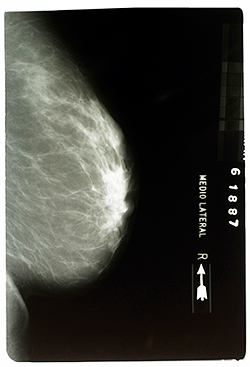

Tous les deux ans, les femmes concernées se voient proposer une invitation pour un examen radiographique des seins (mammographie) dans un centre agréé.

Tous les deux ans, les femmes reçoivent une invitation pour un examen radiographique gratuit des seins.